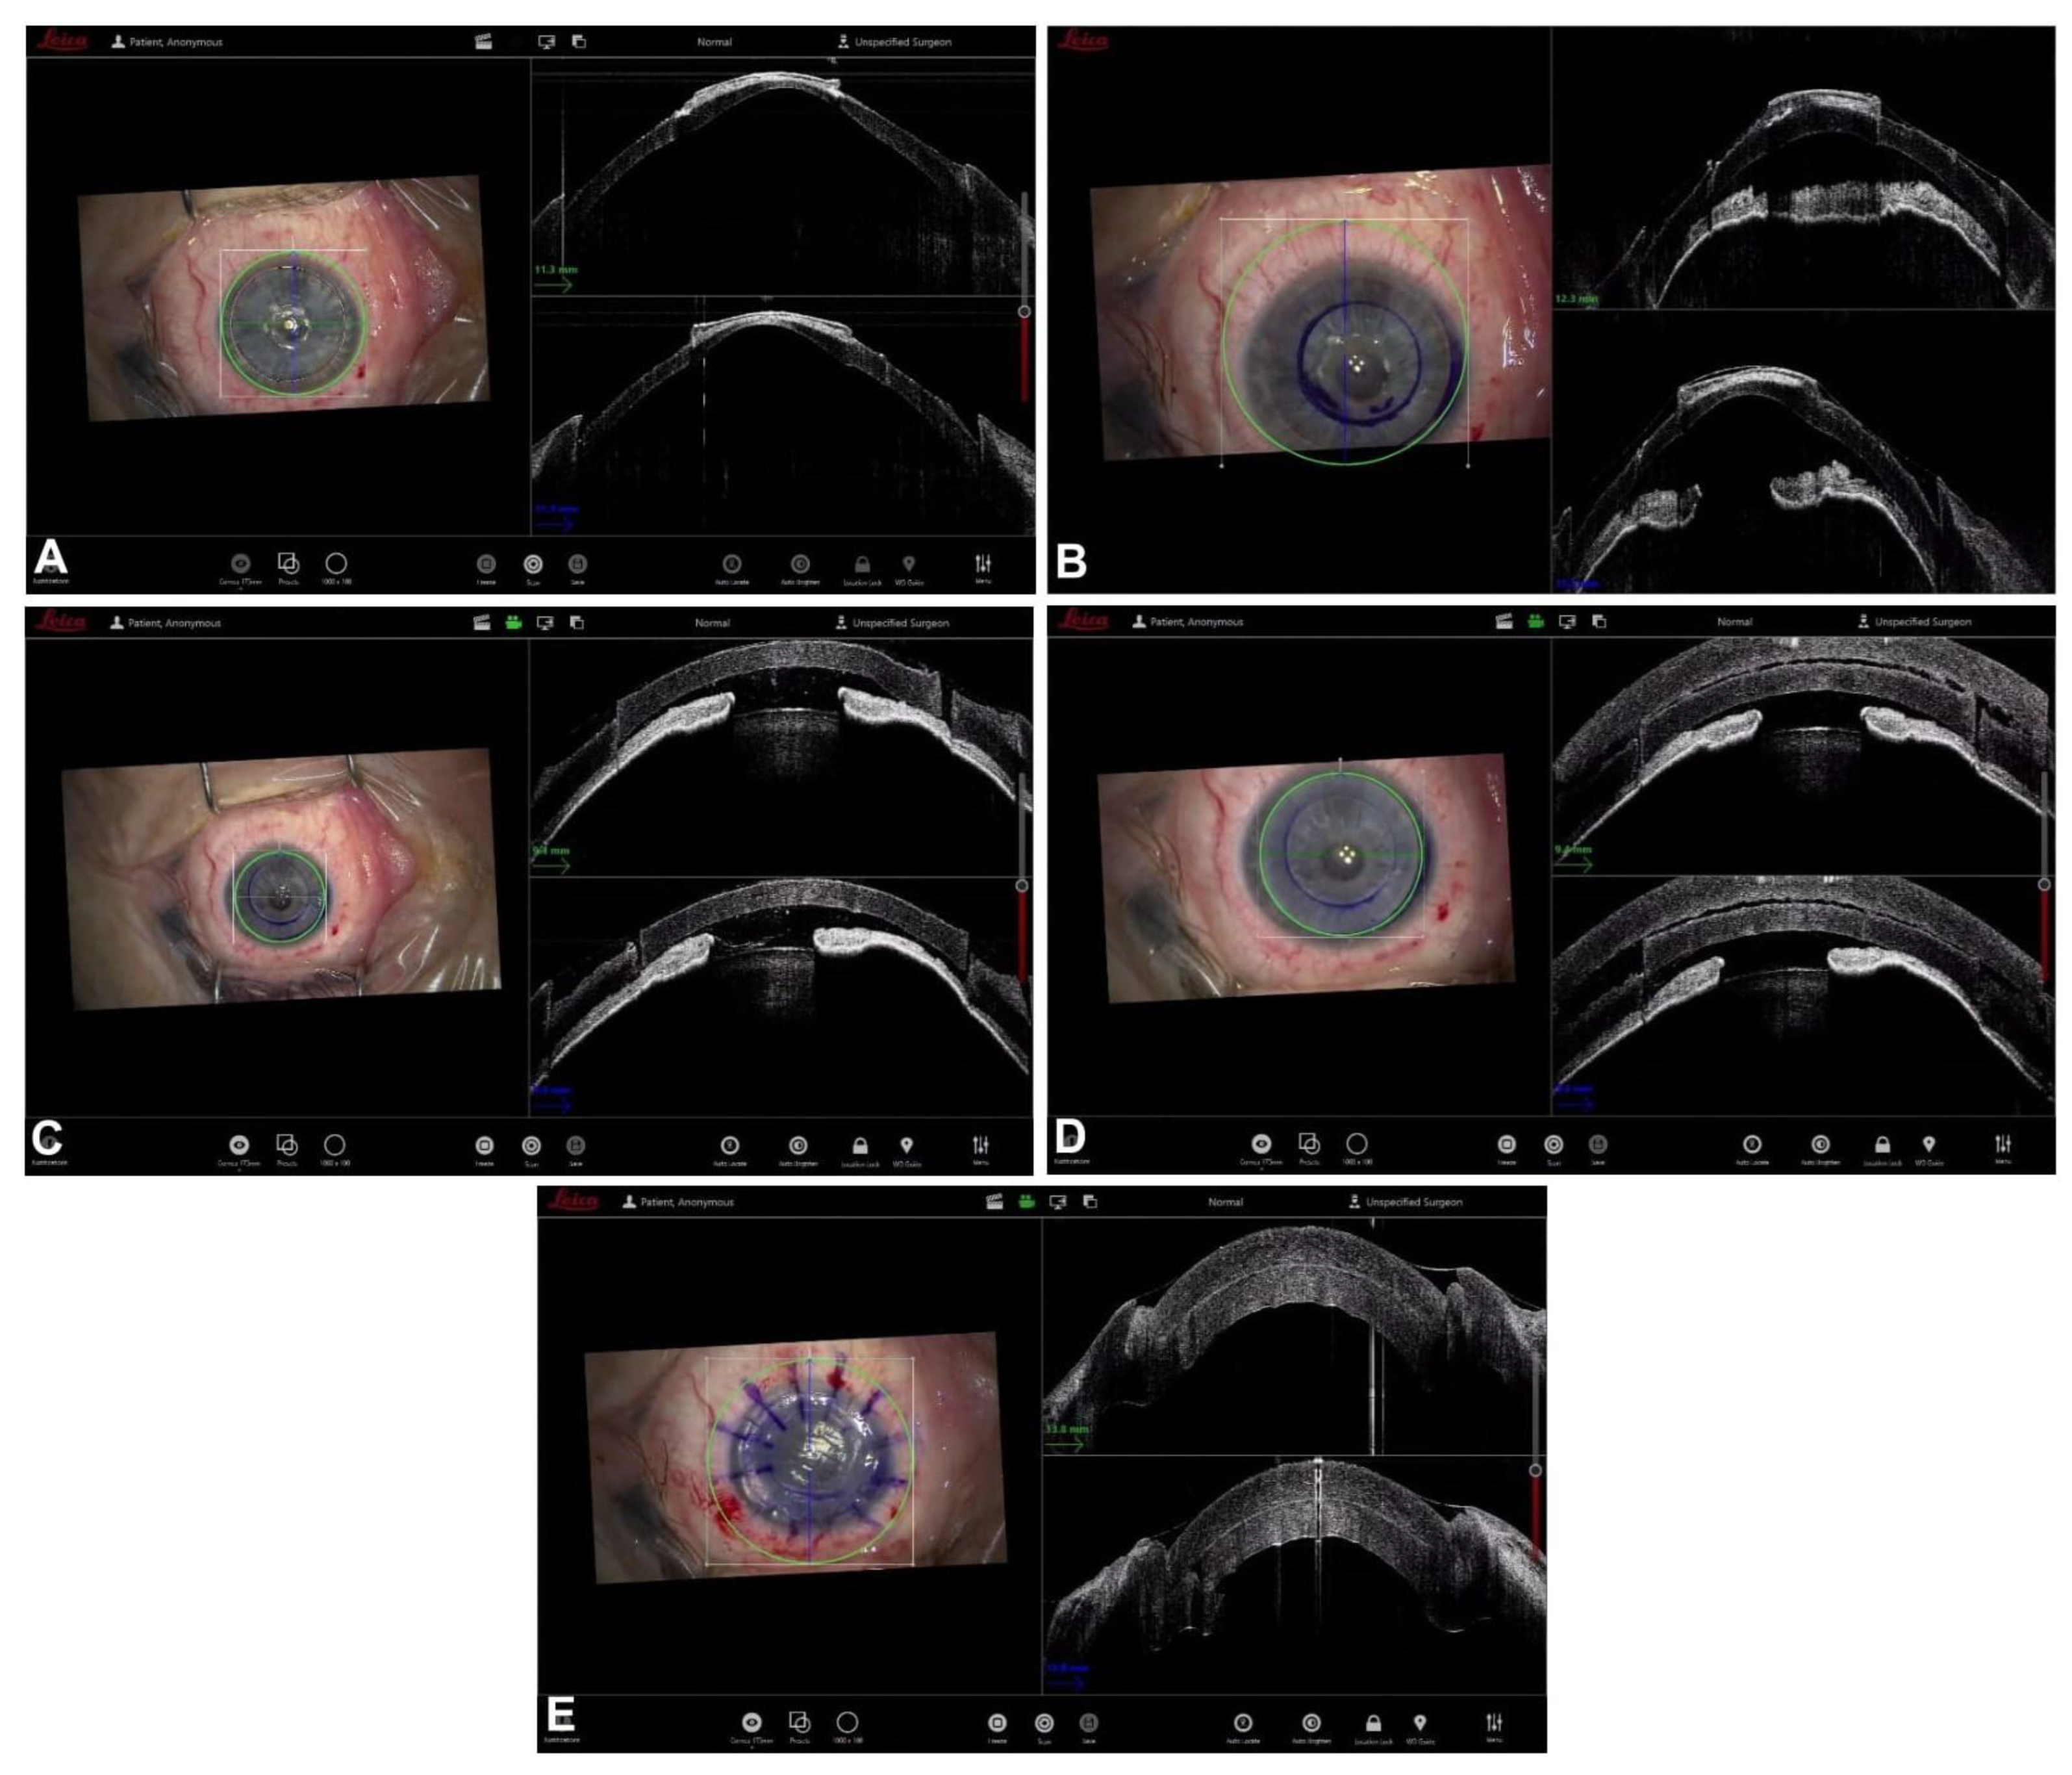

6. Guiding Mushroom Penetrating Keratoplasty

- Busin, M.; Madi, S.; Scorcia, V.; Santorum, P.; Nahum, Y. A Two-Piece Microkeratome-Assisted Mushroom Keratoplasty Improves the Outcomes and Survival of Grafts Performed in Eyes with Diseased Stroma and Healthy Endothelium (An American Ophthalmological Society Thesis). Am. J. Ophthalmol. 2015, 113, T1. [Google Scholar]

- Yu, A.C.; Spena, R.; Fusco, F.; Dondi, R.; Myerscough, J.; Fabbri, F.; Bovone, C.; Busin, M. Long-Term Outcomes of Two-Piece Mushroom Keratoplasty for Traumatic Corneal Scars. Am. J. Ophthalmol. 2021, 236, 20–31. [Google Scholar] [CrossRef] [PubMed]

- Busin, M.; Arffa, R.C. Microkeratome-assisted Mushroom Keratoplasty with Minimal Endothelial Replacement. Am. J. Ophthalmol. 2005, 140, 138–140. [Google Scholar] [CrossRef] [PubMed]